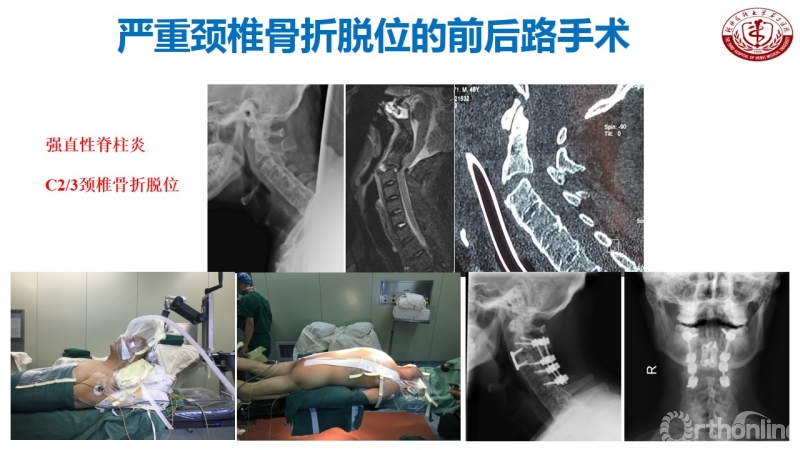

2014年初,丁文元教授像往常一样来到门诊,等在诊室门口的一个小伙子吸引了他的注意。这个小伙子由母亲带着前来就诊,身材高大壮实,但始终不曾抬起头来。经过周密的检查和问诊,丁文元教授得知这个小伙子28岁,名叫大帅(化名),患有强制性脊柱炎颈胸段鹅状畸形,此时也明白了他始终不抬头的原因。

虽然当时河北医科大学第三医院骨科实力雄厚,但是对于此类患者的诊治经验还不多。这位母亲的举动深深触动了丁文元教授的内心,他暗暗下定决心要给大帅一个美好的后半生,当即答应要为其进行手术治疗。

患者资料

门诊结束后,丁文元教授立刻带领团队成员开始查阅大量相关文献,为大帅的手术进行充足的准备和周密的计划。幸运的是手术很顺利,术后复查各项指标恢复良好,大帅的头也抬起了来了,脸上洋溢着久违的笑容,这给了医生和患者家庭极大的信心。

手术步骤